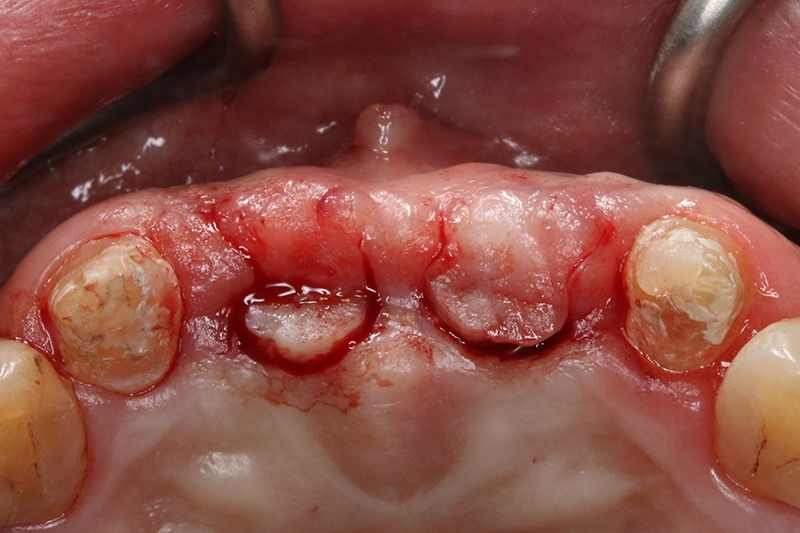

植體植入,置放於理想的水平與垂至高度位置

縫合傷口